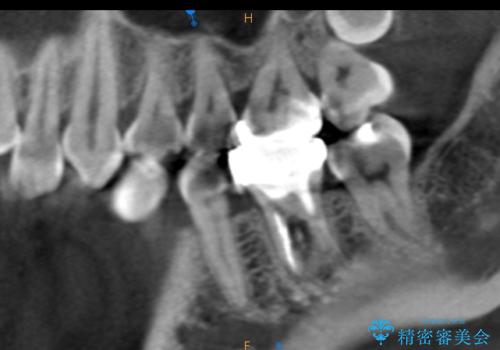

その過程で左下の6番目の歯は治療が必要な状態であることが分かり、被せ物を外して内部を確認してみると根が破折してしまっていることが判明しました。

歯が深い位置で破折している場合は基本的には抜歯が選択されます。

様々な治療プランを患者さんと相談させて頂き、最終的にインプラントで噛み合わせを回復させていくこととなり、まず悪くなっている歯を抜歯することから開始しました。